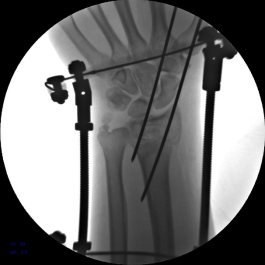

5.使用执行器夹持克氏针,于掌侧穿针,撬拨骨块并使用六轴机器人固定针末端以维持撬拨位置。

6.六轴机器人撬拨骨块过程

7.手术完毕,复位满意